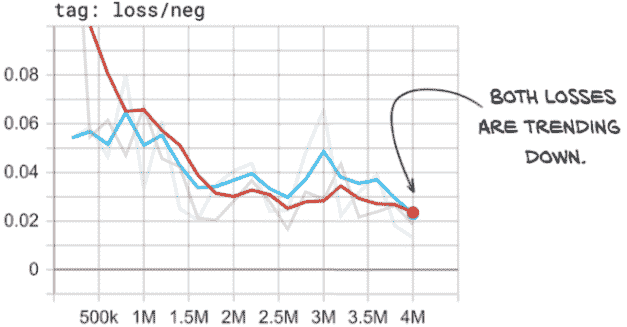

我们所看到的是过拟合的明显迹象。让我们看一下我们在正样本上的损失图,见图 12.18。

图 12.18 我们的正损失显示出明显的过拟合迹象,因为训练损失和验证损失趋势不同。

在这里,我们可以看到我们的正样本的训练损失几乎为零–每个正样本训练样本都得到了几乎完美的预测。然而,我们的正样本的验证损失却在增加,这意味着我们的实际表现可能正在变差。在这一点上,最好停止训练脚本,因为模型不再改进。

提示 通常,如果您的模型在训练集上的表现正在提高,而在验证集上表现变差,那么模型已经开始过拟合。

然而,我们必须注意检查正确的指标,因为这种趋势只发生在我们的正损失上。如果我们看一下我们的整体损失,一切似乎都很好!这是因为我们的验证集不平衡,所以整体损失被我们的负样本所主导。正如图 12.19 所示,我们在我们的负样本中没有看到相同的发散行为。相反,我们的负损失看起来很好!这是因为我们有 400 倍的负样本,所以模型要记住个别细节要困难得多。然而,我们的正训练集只有 1,215 个样本。虽然我们多次重复这些样本,但这并不会使它们更难记忆。模型正在从泛化原则转变为基本上记住这 1,215 个样本的怪癖,并声称不属于这几个样本之一的任何东西都是负样本。这包括负训练样本和我们验证集中的所有内容(正负样本都有)。

图 12.19 我们的负损失没有显示过拟合的迹象